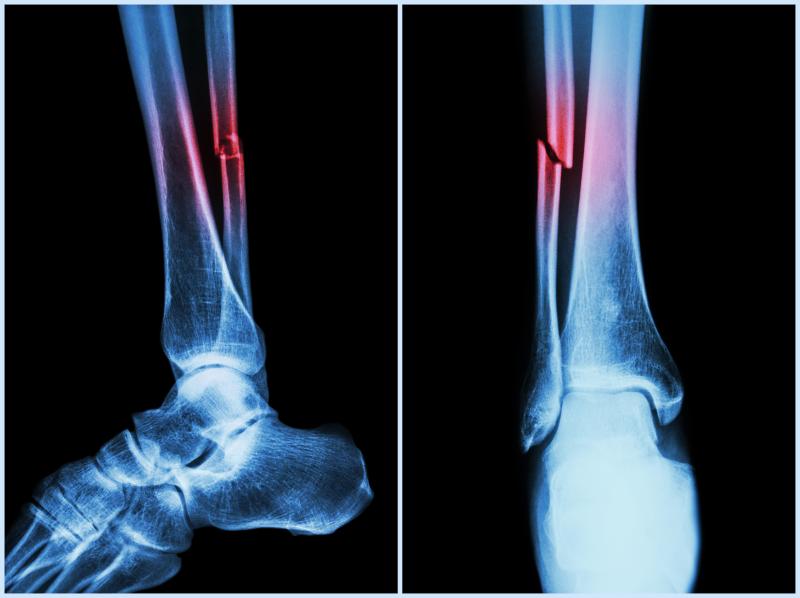

In patients with traumatic brain injury (TBI) who sustained extremity fractures, fracture fixation performed within 24 hours after TBI does not appear to result in worse functional outcomes as opposed to when performed beyond 24 hours, according to a study.